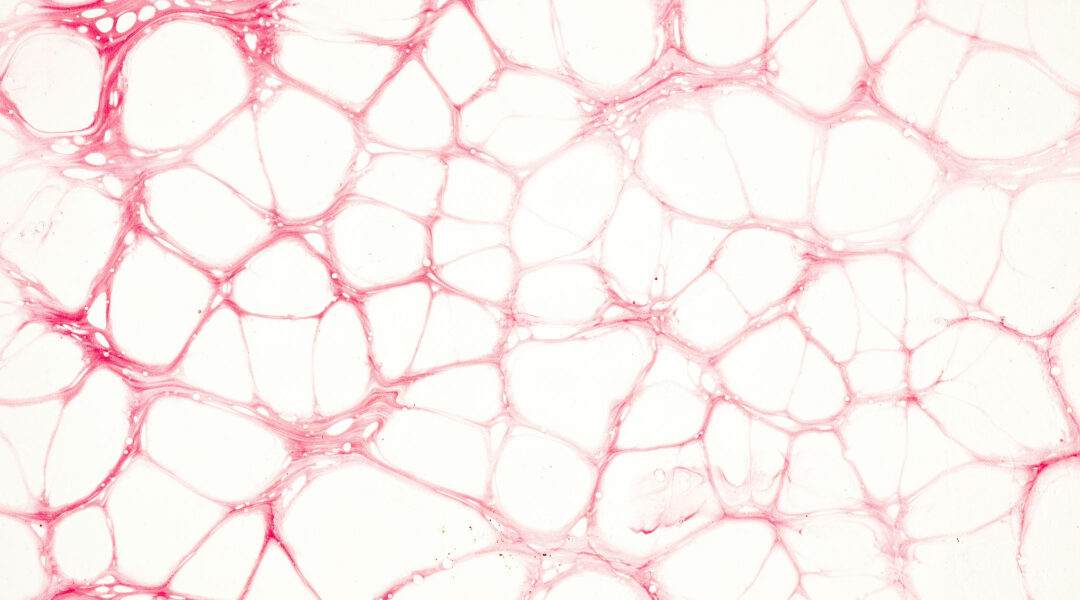

PF4 is a substance produced by platelets, which are tiny blood cells that help our bodies respond to injuries and form blood clots. What scientists have now discovered is that PF4 does more than just that – it can make your brain feel younger and sharper, no matter your age!